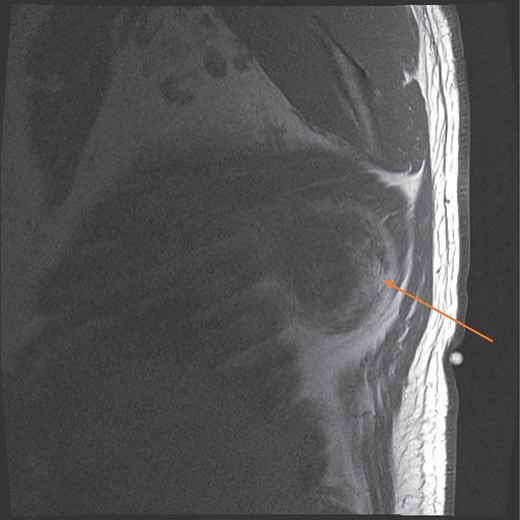

MRI sagittal view showing the circumscribed right sided tumour with a pseudocapsule, at the infrascapular region (orange arrow).